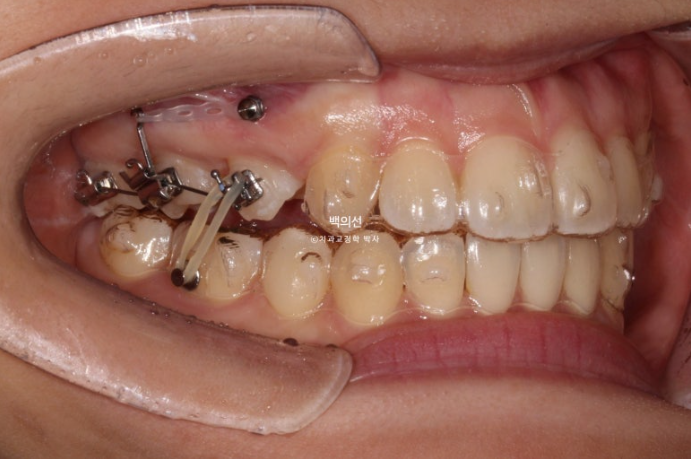

23.10

그리고 치료 시작 10개월차, 교합면 사진을 보면 마치 발치공간이 다 닫힌것 처럼 보입니다.

그러나 발치공간으로 어금니가 쓰러진걸 볼 수 있습니다.

이제 더이상 재제작을 미룰 수 없고 쓰러진 어금니도 세워야합니다.

쓰러진 어금니를 세우는 데에는 인비절라인이 효과적인 경우도 있고 브라켓이 효과적인 경우도 있습니다.

이 경우 쓰러진 정도가 심해 부라켓을 붙여 부분교정으로 쓰러진 어금니를 세우기로 합니다.

23년 10월부터 5개월간 어금니에 부분적으로 브라켓을 붙이고 나사를 심고 고무줄을 걸며 쓰러진 어금니를 세웠습니다.